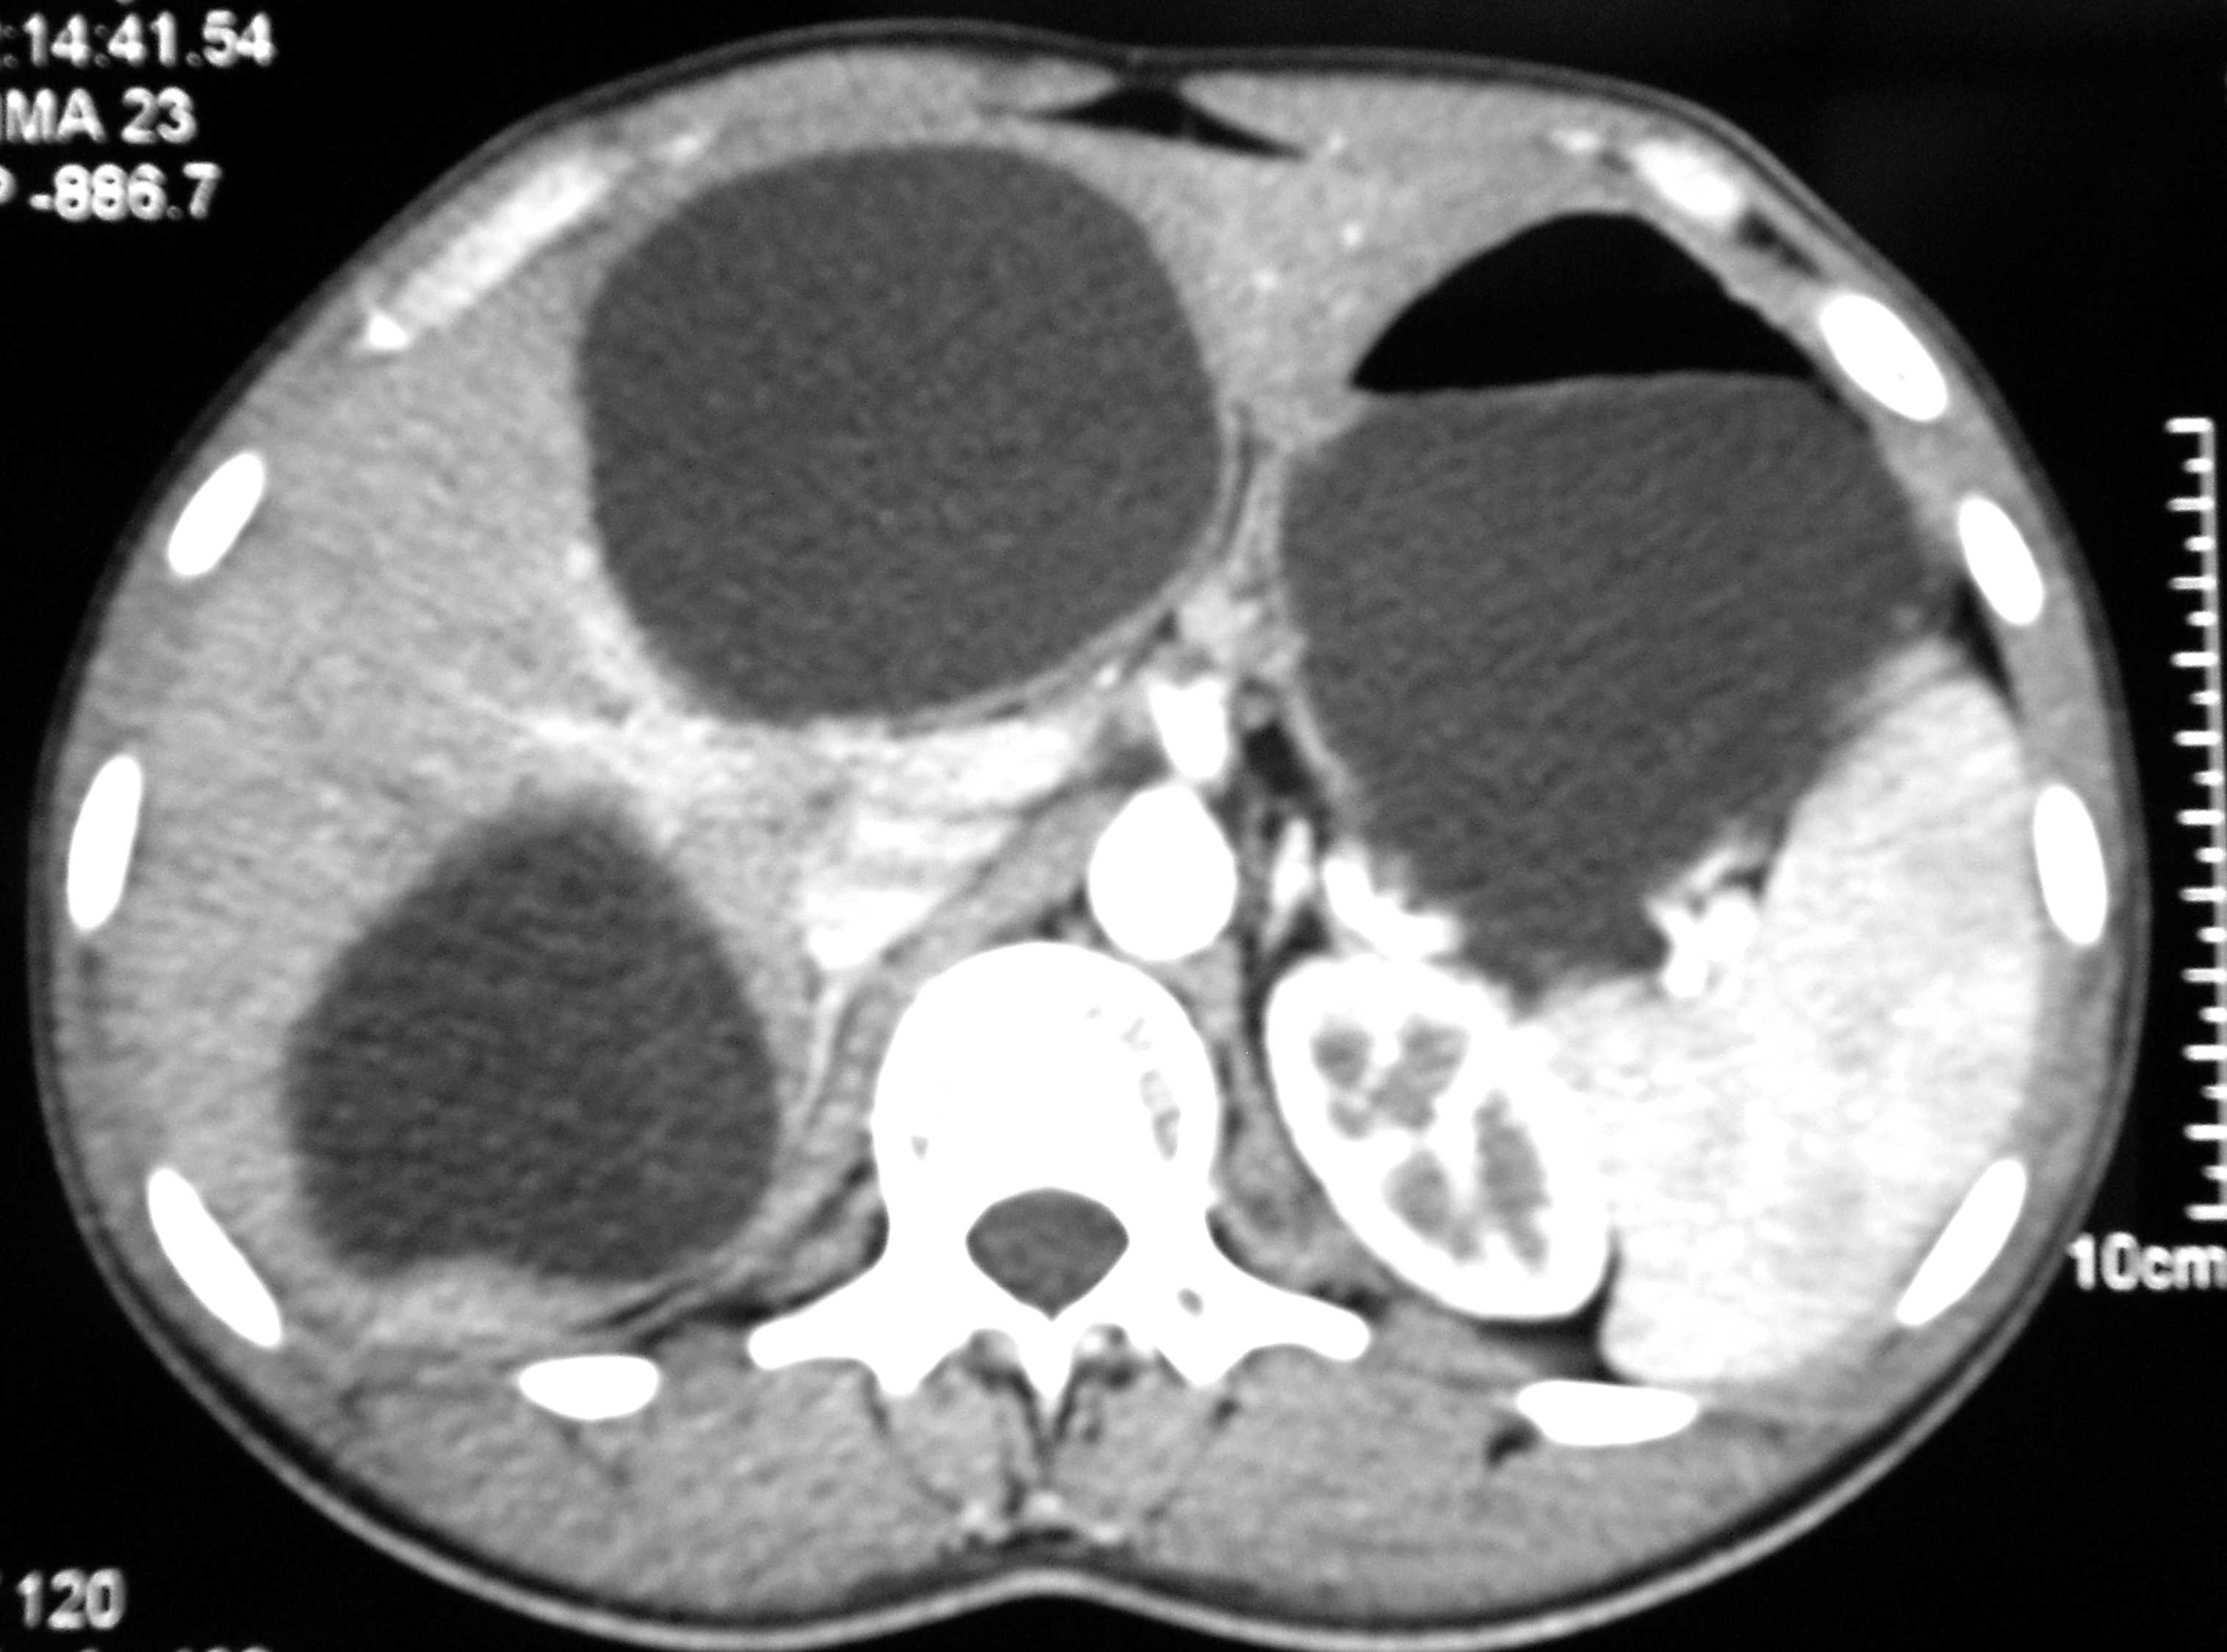

On admission, oral temperature was 100°F, pulse rate was 100/minute, Blood Pressure was 120/80 mmHg, Respiratory rate was 30/min. There was decreased air entry on left lung auscultation and one Intercostal drain (ICD) in situ on left side. Per abdomen examination was insignificant except hepatomegaly. Chest X-ray PA view after aspiration showed hydropneumothorax with clear-cut cyst margins on the left lower region with ICD inside (Figure 1). CECT abdomen and chest revealed two hydatid cysts in the right lobe of the liver (Figures 2 & 3). After all preoperative evaluation, patient was found fit for the surgery. His all hematologic and biochemical parameters were within normal limits. Therefore, it was planned to deal with the lung and liver hydatids at the same sitting under general anesthesia first with liver followed by lung hydatid cyst.

Figure 2 CECT Abdomen revealed hydatid cyst in both the lobes of liver.